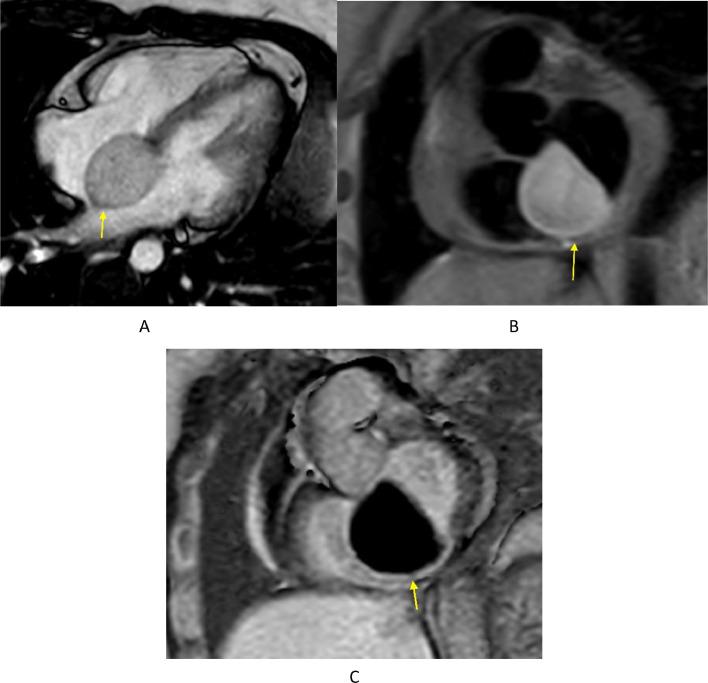

The authors report a case of pathologically proven intracardiac bronchogenic cyst embedded within the interatrial septum of a 30-year-old woman presenting with chest pain and first-degree AV block. Multimodality imaging played an essential role in the discovery, investigation, and diagnosis of this extremely rare entity.

作者报告了一例经病理证实的心脏内支气管源性囊肿病例,该囊肿位于一名30岁女性的房间隔内,患者表现为胸痛和一度房室传导阻滞。多模态成像在这一极其罕见疾病的发现、检查和诊断中发挥了重要作用。